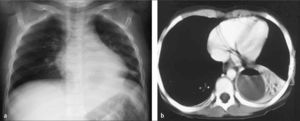

En posición de pies, el derrame se observa radiológicamente como ocupación de los recesos pleuro-diafragmáticos laterales y posteriores cuando es de escasa cuantía y como una opacidad homogénea, que vela el aspecto inferior del hemitórax, con un contorno que asciende lateralmente en proyección frontal dando la clásica incurvación con aspecto de menisco en relación al margen superior del derrame (Figura 6). Si este contenido líquido se encuentra libre en el espacio pleural, se movilizará con los cambios de posición y así por ejemplo, en decúbito se distribuirá homogéneamente en el aspecto posterior del espacio pleural observándose radiológicamente como un hemitórax más denso que el contralateral (4).